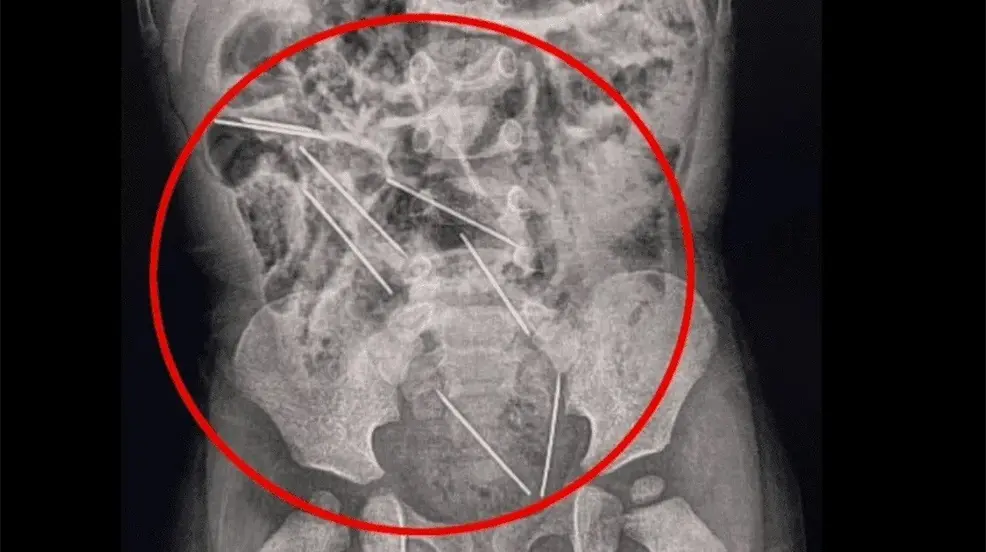

La madre del menor se percató de lo ocurrido, por lo que de inmediato fue llevado al hospital en donde fue sometido a una exploración, en donde radiografías mostraron que las agujas estaban dentro del sistema digestivo del niño.

Algunas de las agujas, se encontraban muy cerca de los órganos vitales del bebé, por lo que de inmediato los médicos lo sometieron a una cirugía de casi dos horas para retirar las agujas, y también recibió tratamiento por una pequeña lesión en el intestino delgado.De acuerdo con especialistas, cuando una persona traga un objeto extraño, este puede atorarse en el tracto gastrointestinal del esófago al colon, lo que le provocó una infección, una oclusión o ruptura en los órganos vitales.